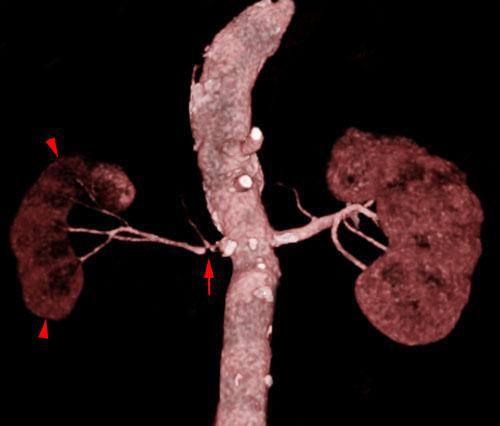

Infartos renales múltiples